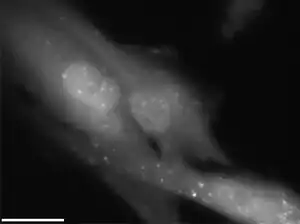

| Radiation causes cellular degradation by autophagy. | |